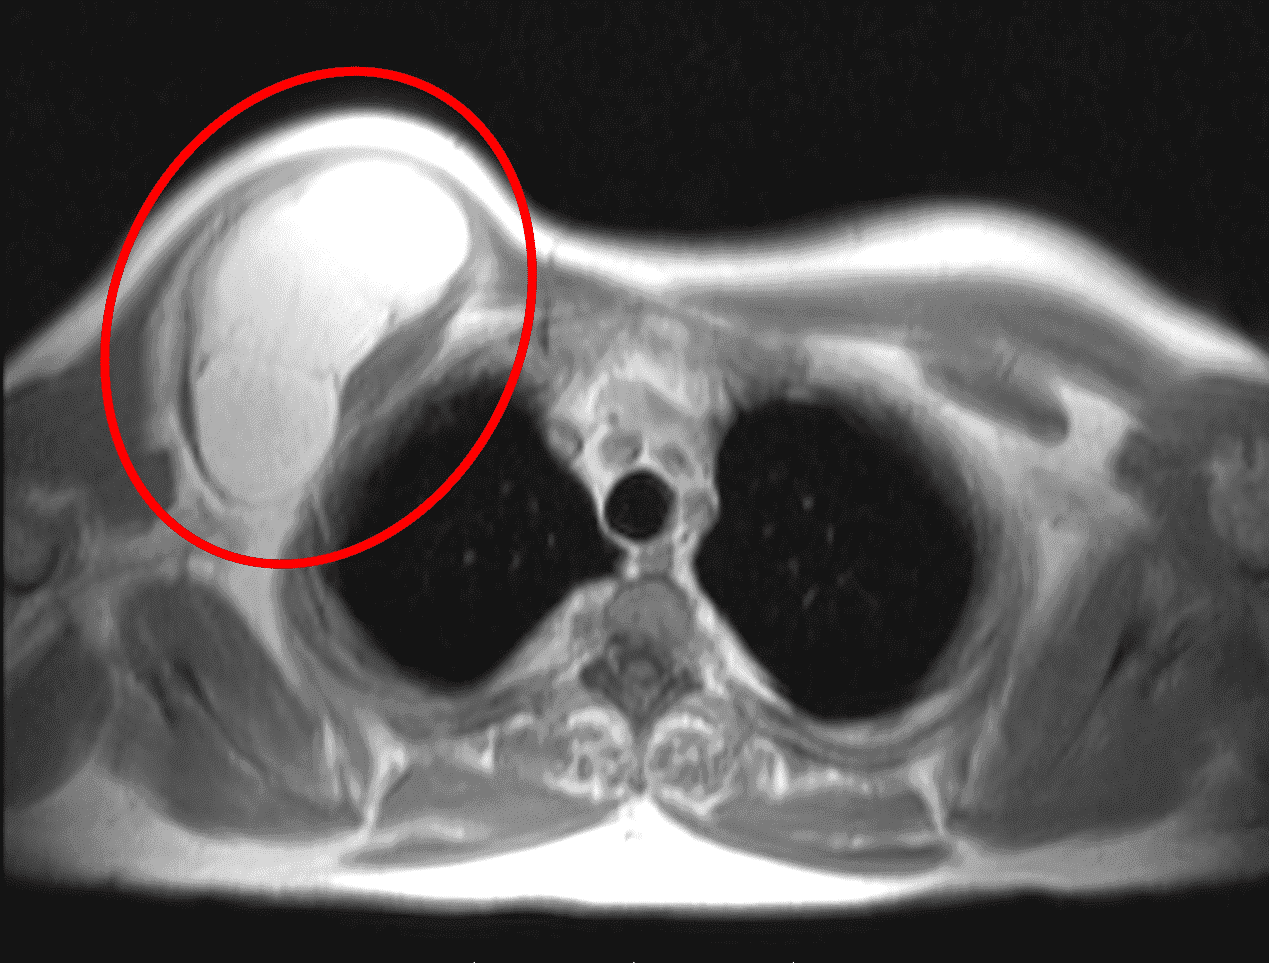

Для злоякісних утворень оптимальнішими є контрастні фази (зобр. 2). Фази STIR допомагають продемонструвати ступінь перитуморального набряку. Якщо МРТ недоступна, комп’ютерна томографія (КТ) є наступним найбільш інформативним методом візуалізації, що забезпечує детальні крос-секційні зображення, які можуть допомогти визначити розмір і ступінь ураження, про яке йдеться. Ураження лімфатичних вузлів не є поширеним при ETSTS, але патологічна лімфаденопатія, виявлена під час фізикального обстеження або виявлена на візуалізації, якщо вона є, повинна спонукати до поглиблення діагностичного пошуку.

Зобр. 2: На МРТ показана веретеноклітинна саркома високої ступеня злоякісності у задній ділянці правого плеча. А) Т1 фаза показує злоякісну пухлину, яка ізоінтенсивна до м’язової тканини.

Figure 2: (B) Постконтрастна фаза показує гіперінтенсивну пухлину.